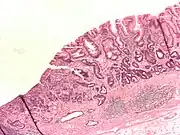

- Gastric adenocarcinoma is a malignant epithelial tumour, originating from glandular epithelium of the gastric mucosa. Stomach cancers are about 90% adenocarcinomas.[67] Histologically, there are two major types of gastric adenocarcinoma (Lauren classification): intestinal type or diffuse type. Adenocarcinomas tend to aggressively invade the gastric wall, infiltrating the muscularis mucosae, the submucosa and then the muscularis propria. Intestinal type adenocarcinoma tumour cells describe irregular tubular structures, harbouring pluristratification, multiple lumens, reduced stroma ("back to back" aspect). Often, it associates intestinal metaplasia in neighbouring mucosa. Depending on glandular architecture, cellular pleomorphism and mucosecretion, adenocarcinoma may present 3 degrees of differentiation: well, moderate and poorly differentiated. Diffuse type adenocarcinoma (mucinous, colloid, linitis plastica or leather-bottle stomach) tumour cells are discohesive and secrete mucus, which is delivered in the interstitium, producing large pools of mucus/colloid (optically "empty" spaces). It is poorly differentiated. In signet-ring cell carcinomas, the mucus remains inside the tumour cell and pushes the nucleus to the periphery, giving rise to signet-ring cells.

Poor to moderately differentiated adenocarcinoma of the stomach. H&E stain.

Adenocarcinoma of the stomach and intestinal metaplasia. H&E stain.